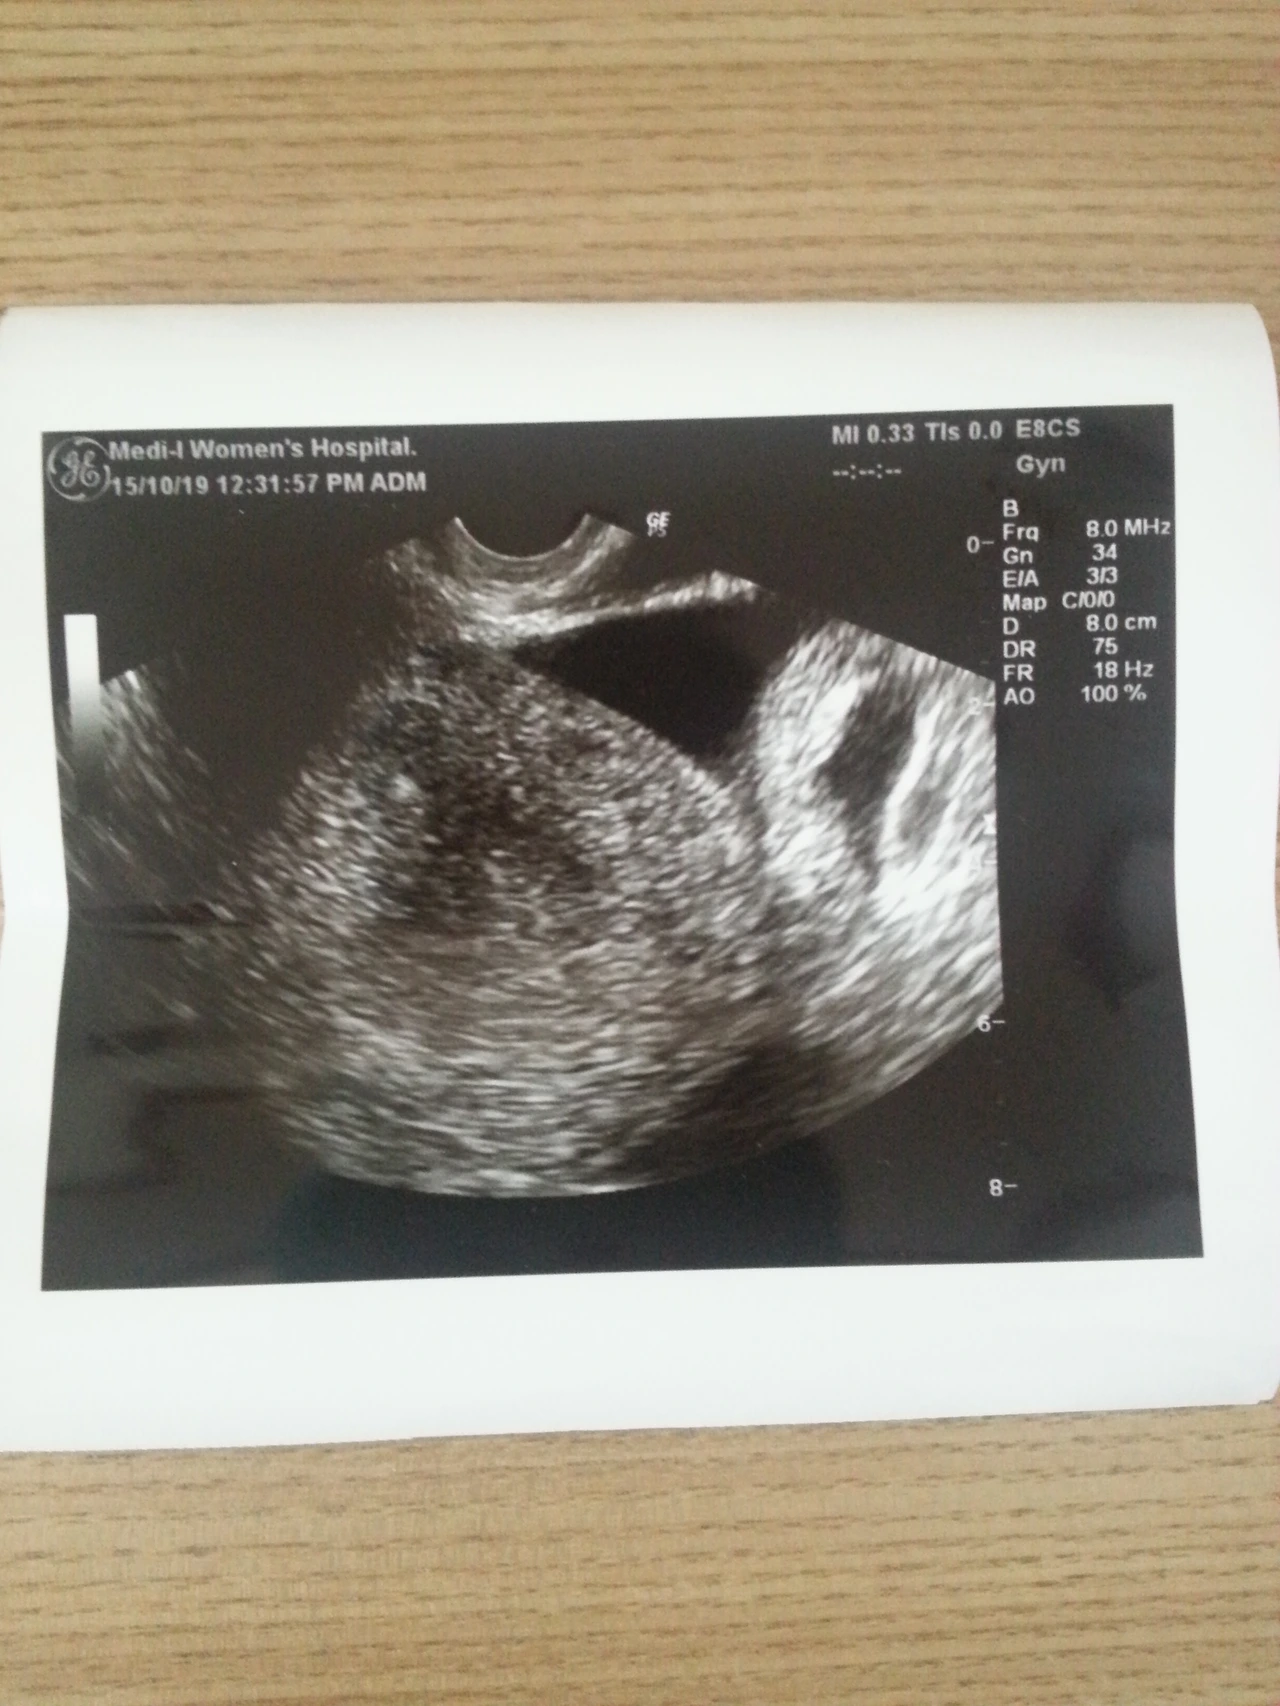

주말 내내 남편이 청소며 설거지며 다 해줘서 공주처럼 지냈다. 편하고 안정된 마음으로 잘 지내고, 오늘 병원에 가는 날임에도 딱히 걱정도 없었다. 피검사를 할 줄 알았는데 초음파를 보자는 선생님. 아기집이 보일 시기라고 한다. 하지만 가득 찬 복수만 보이고 아기집은 아무리 찾아도 보이지 않았다. 지난주까지 임신 수치가 잘 올랐는데ᆢ 다시 주사를 맞고, 피검사를 했다. 수치가 1000 이상이 나와야 수요일 날 아기집을 확인할 수 있다고 한다. 결과는 내일 나온다. 휴ᆢ 집에 돌아가는 길에 엄마의 부재중 통화가 있어 전화했더니, 대신 주문해 주었던 뽕 머리가 이게 아니라면서. 엄마는 딸이 아픈데도 오직 자기 얘기뿐이다. 그나마 짜증을 겨우 참고 알아서 좀 하시라고. 그리고 그 짜증은 남편한테 고스란히 돌아갔다. 집에 도착해서 만두로 고픈 배를 달래고 나니까 엄마한테 미안한 마음에 다시 문자를 보냈다. 정말 아무것도 신경 쓰고 싶지 않은데 엄마가 날 신경 쓰이게 한다. 아직도 엄마가 좋지 않다. 어렸을 때처럼ᆢ 이런 내가 엄마가 될 수 있을까?